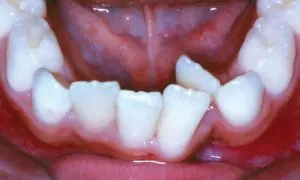

Crowding

Crowding occurs when teeth have insufficient room to erupt from the gum. Crowding can often be corrected by expansion, and many times, tooth removal can be avoided.